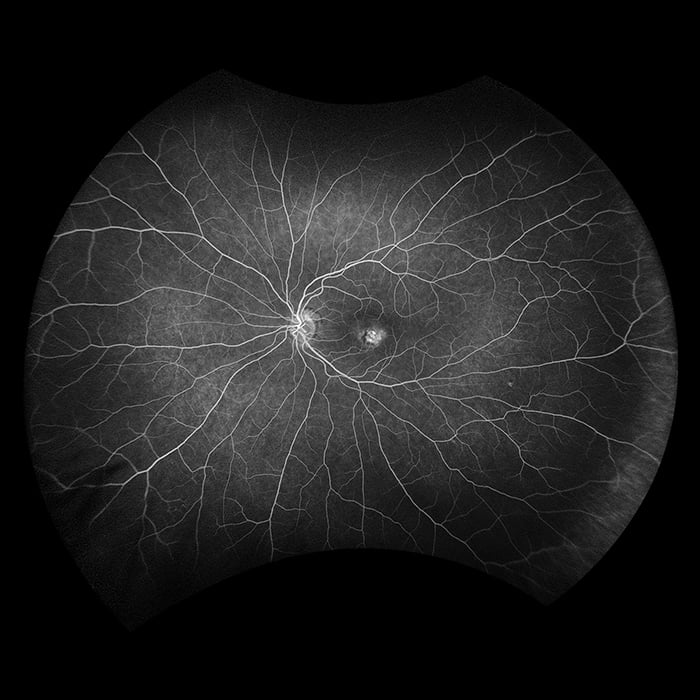

Daytona produces a 200° single shot optomap retinal image of unrivaled clarity in less than ½ second. This fast, easy, patient-friendly, ultra-widefield imaging technology was designed for healthy eye screening and has been shown to improve practice flow and patient engagement.

optomap has been shown to enhance pathology detection and disease management and to improve clinic flow. The Daytona system is the most widely used true UWF imaging device.

optomap Image Modalities

- color rg

- Sensory Retina

- Choroidal

- green af